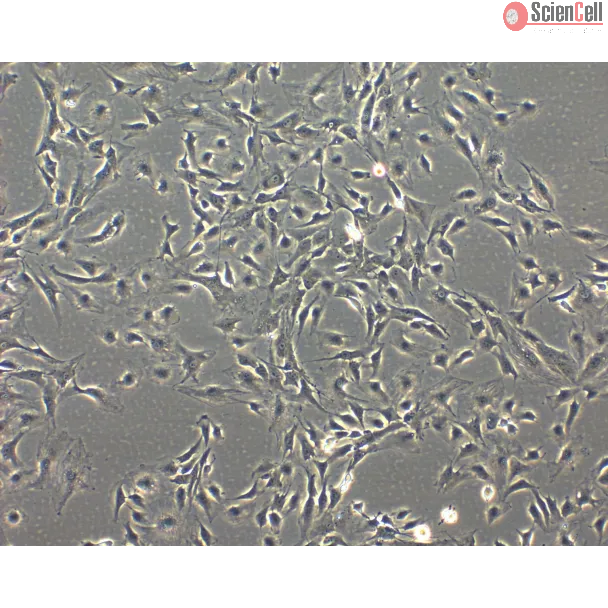

兔虹膜色素上皮细胞

从荷兰兔虹膜分离。RabIPEpiC 在传代一次时进行冷冻保存,并以冻存形式交付。每管含 >5 x 105 个细胞,体积为 1 毫升。

虹膜是具有可变孔径的有色圆盘,可控制瞳孔大小及到达视网膜的光量。虹膜由前界层、基质层、扩瞳肌层和后方色素上皮组成。虹膜色素上皮细胞(IPEpiC)与视网膜色素上皮细胞(RPE)具有相同的胚胎起源,因此表现出与 RPE 类似的功能特性,包括光感受器的更新和营养因子的合成。研究表明,将 IPEpiC 移植到视网膜下空间可抑制异常新生血管生成和光感受器退化,这提示 IPEpiC 移植未来可能用于治疗视网膜疾病。IPEpiC 也可能作为神经退行性疾病治疗的细胞来源。

来自 ScienCell 研究实验室的 RabIPEpiC 分离自荷兰兔虹膜。RabIPEpiC 在传代一次时进行冷冻保存并以冻存形式交付。每管含 >5 x 105 个细胞,体积为 1 毫升。RabIPEpiC 通过针对细胞角蛋白-18的抗体进行免疫荧光表征。RabIPEpiC 对支原体、细菌、酵母和真菌均为阴性。RabIPEpiC 保证可在 ScienCell 提供的培养条件下继续培养;但由于扩增能力有限,不建议进行亚培养。